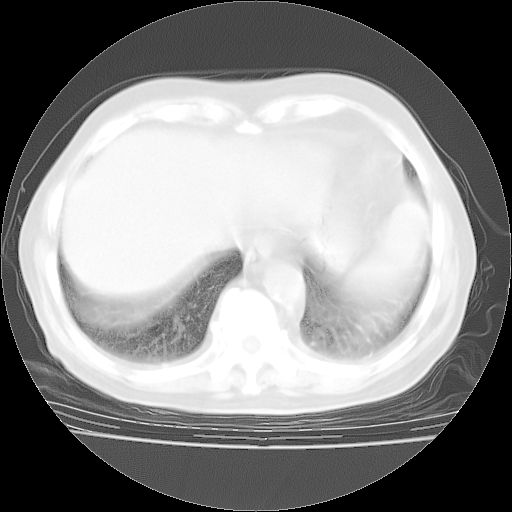

4月28日肺部CT——再次出现类似去年5月9日——透光度降低,“间质性”改变。

4月28日肺部CT——再次出现类似去年5月9日——磨玻璃样、间有“粟粒样”改变。